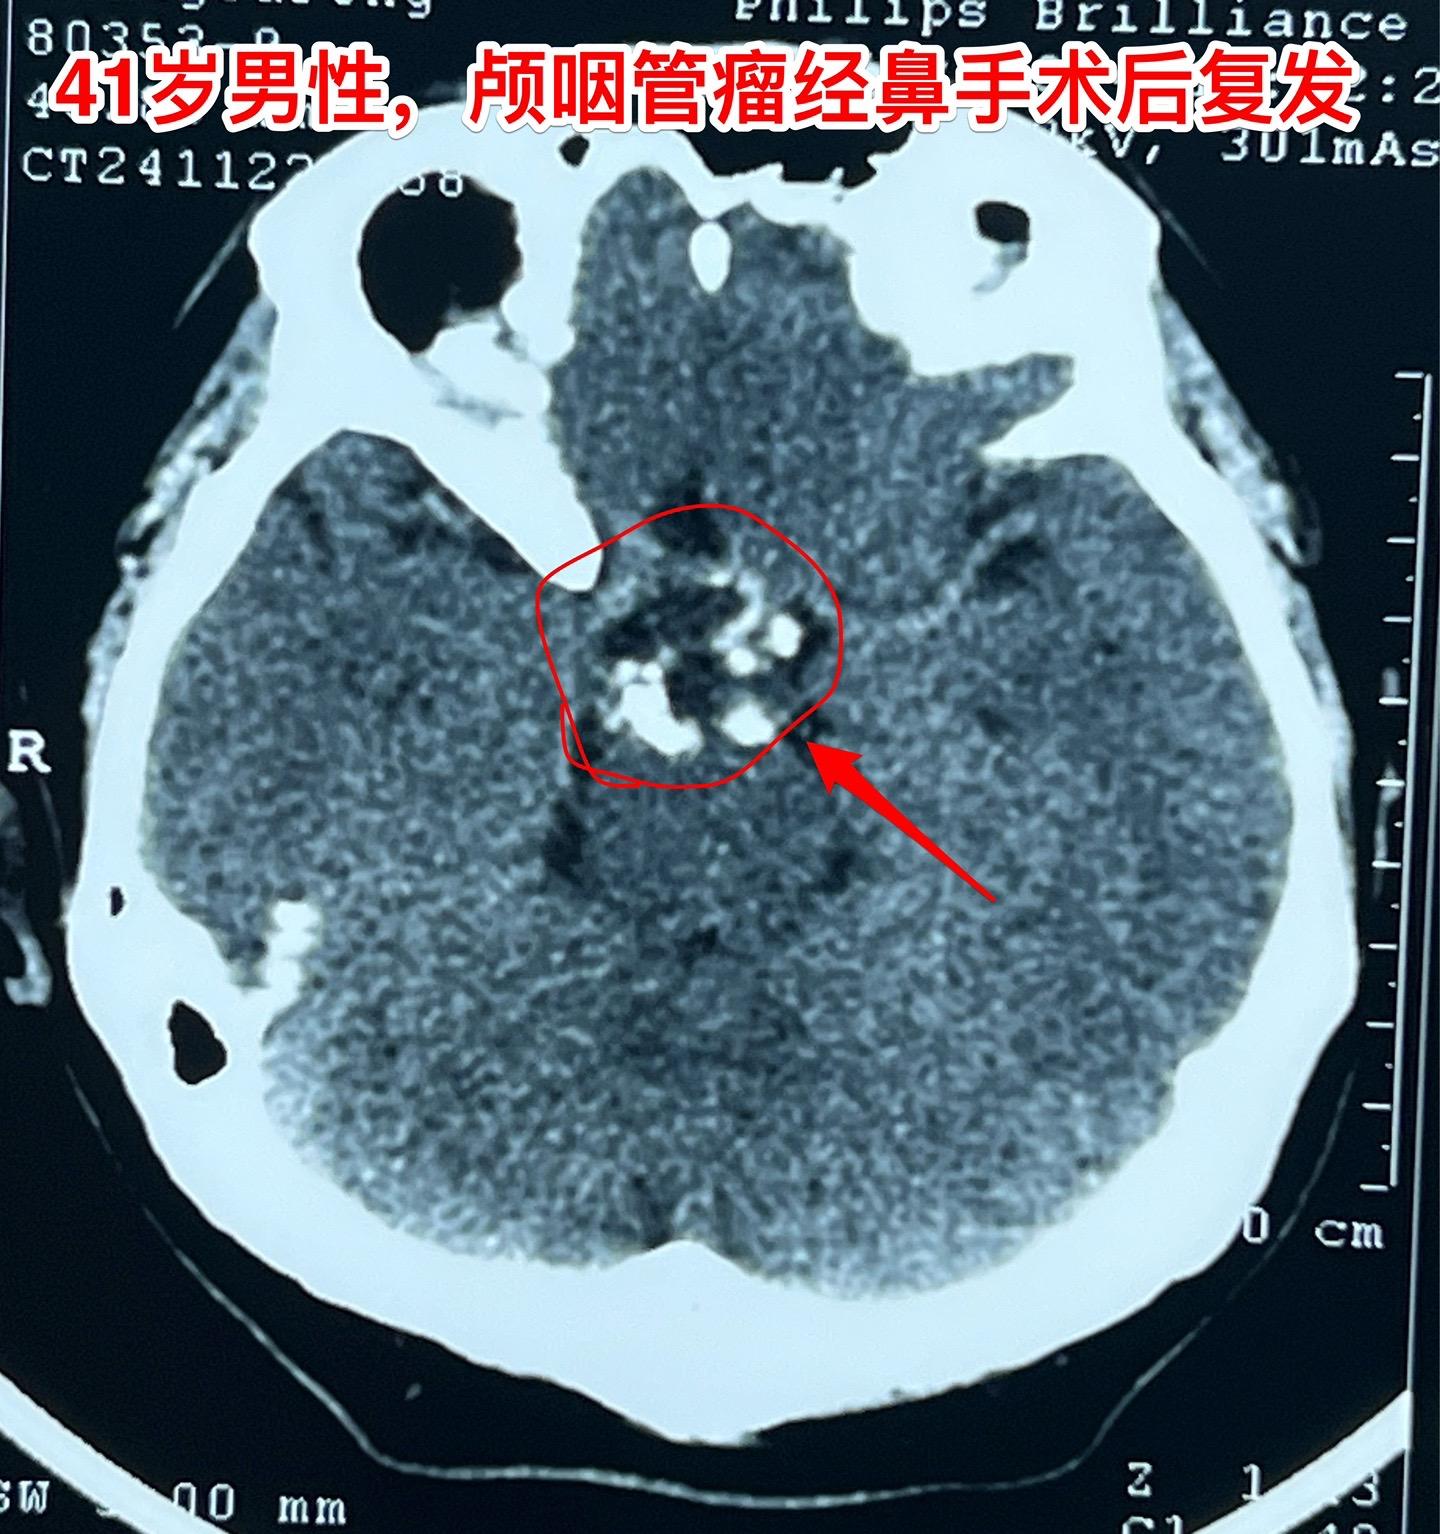

又一个经鼻手术后复发的颅咽管瘤。41岁的大连市男性,三年前因视力下降在辽宁省作了经鼻手术切除颅咽管瘤。手术后视力好转了,当时术后三个月复查磁共振显示肿瘤有残留。随后观察,多次复查磁共振显示肿瘤体积在增大,而且再次出现视力下降。如图所示,肿瘤有钙化,是典型的造釉性颅咽管瘤,一部分肿瘤位于鞍背后方,手术切除肿瘤还是有难度的。 2024年11月来找我办理住院手续,11月29日作了开颅手术(十一月的最后一个手术)。